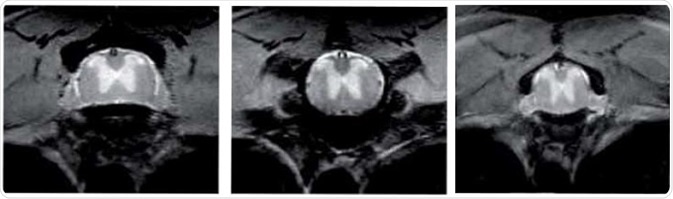

Mouse spine imaging

The below picture shows high-resolution (46 x 46 µm in-plane) mouse spine imaging acquired using TurboRARE, captured in less than 7 minutes at 9.4 T, clearly differentiating white and gray matter and revealing fine anatomical details, such as cerebrospinal fluid, vessels, and root ganglions.

Mouse Spine lmaging. Image Credit: Bruker BioSpin Group